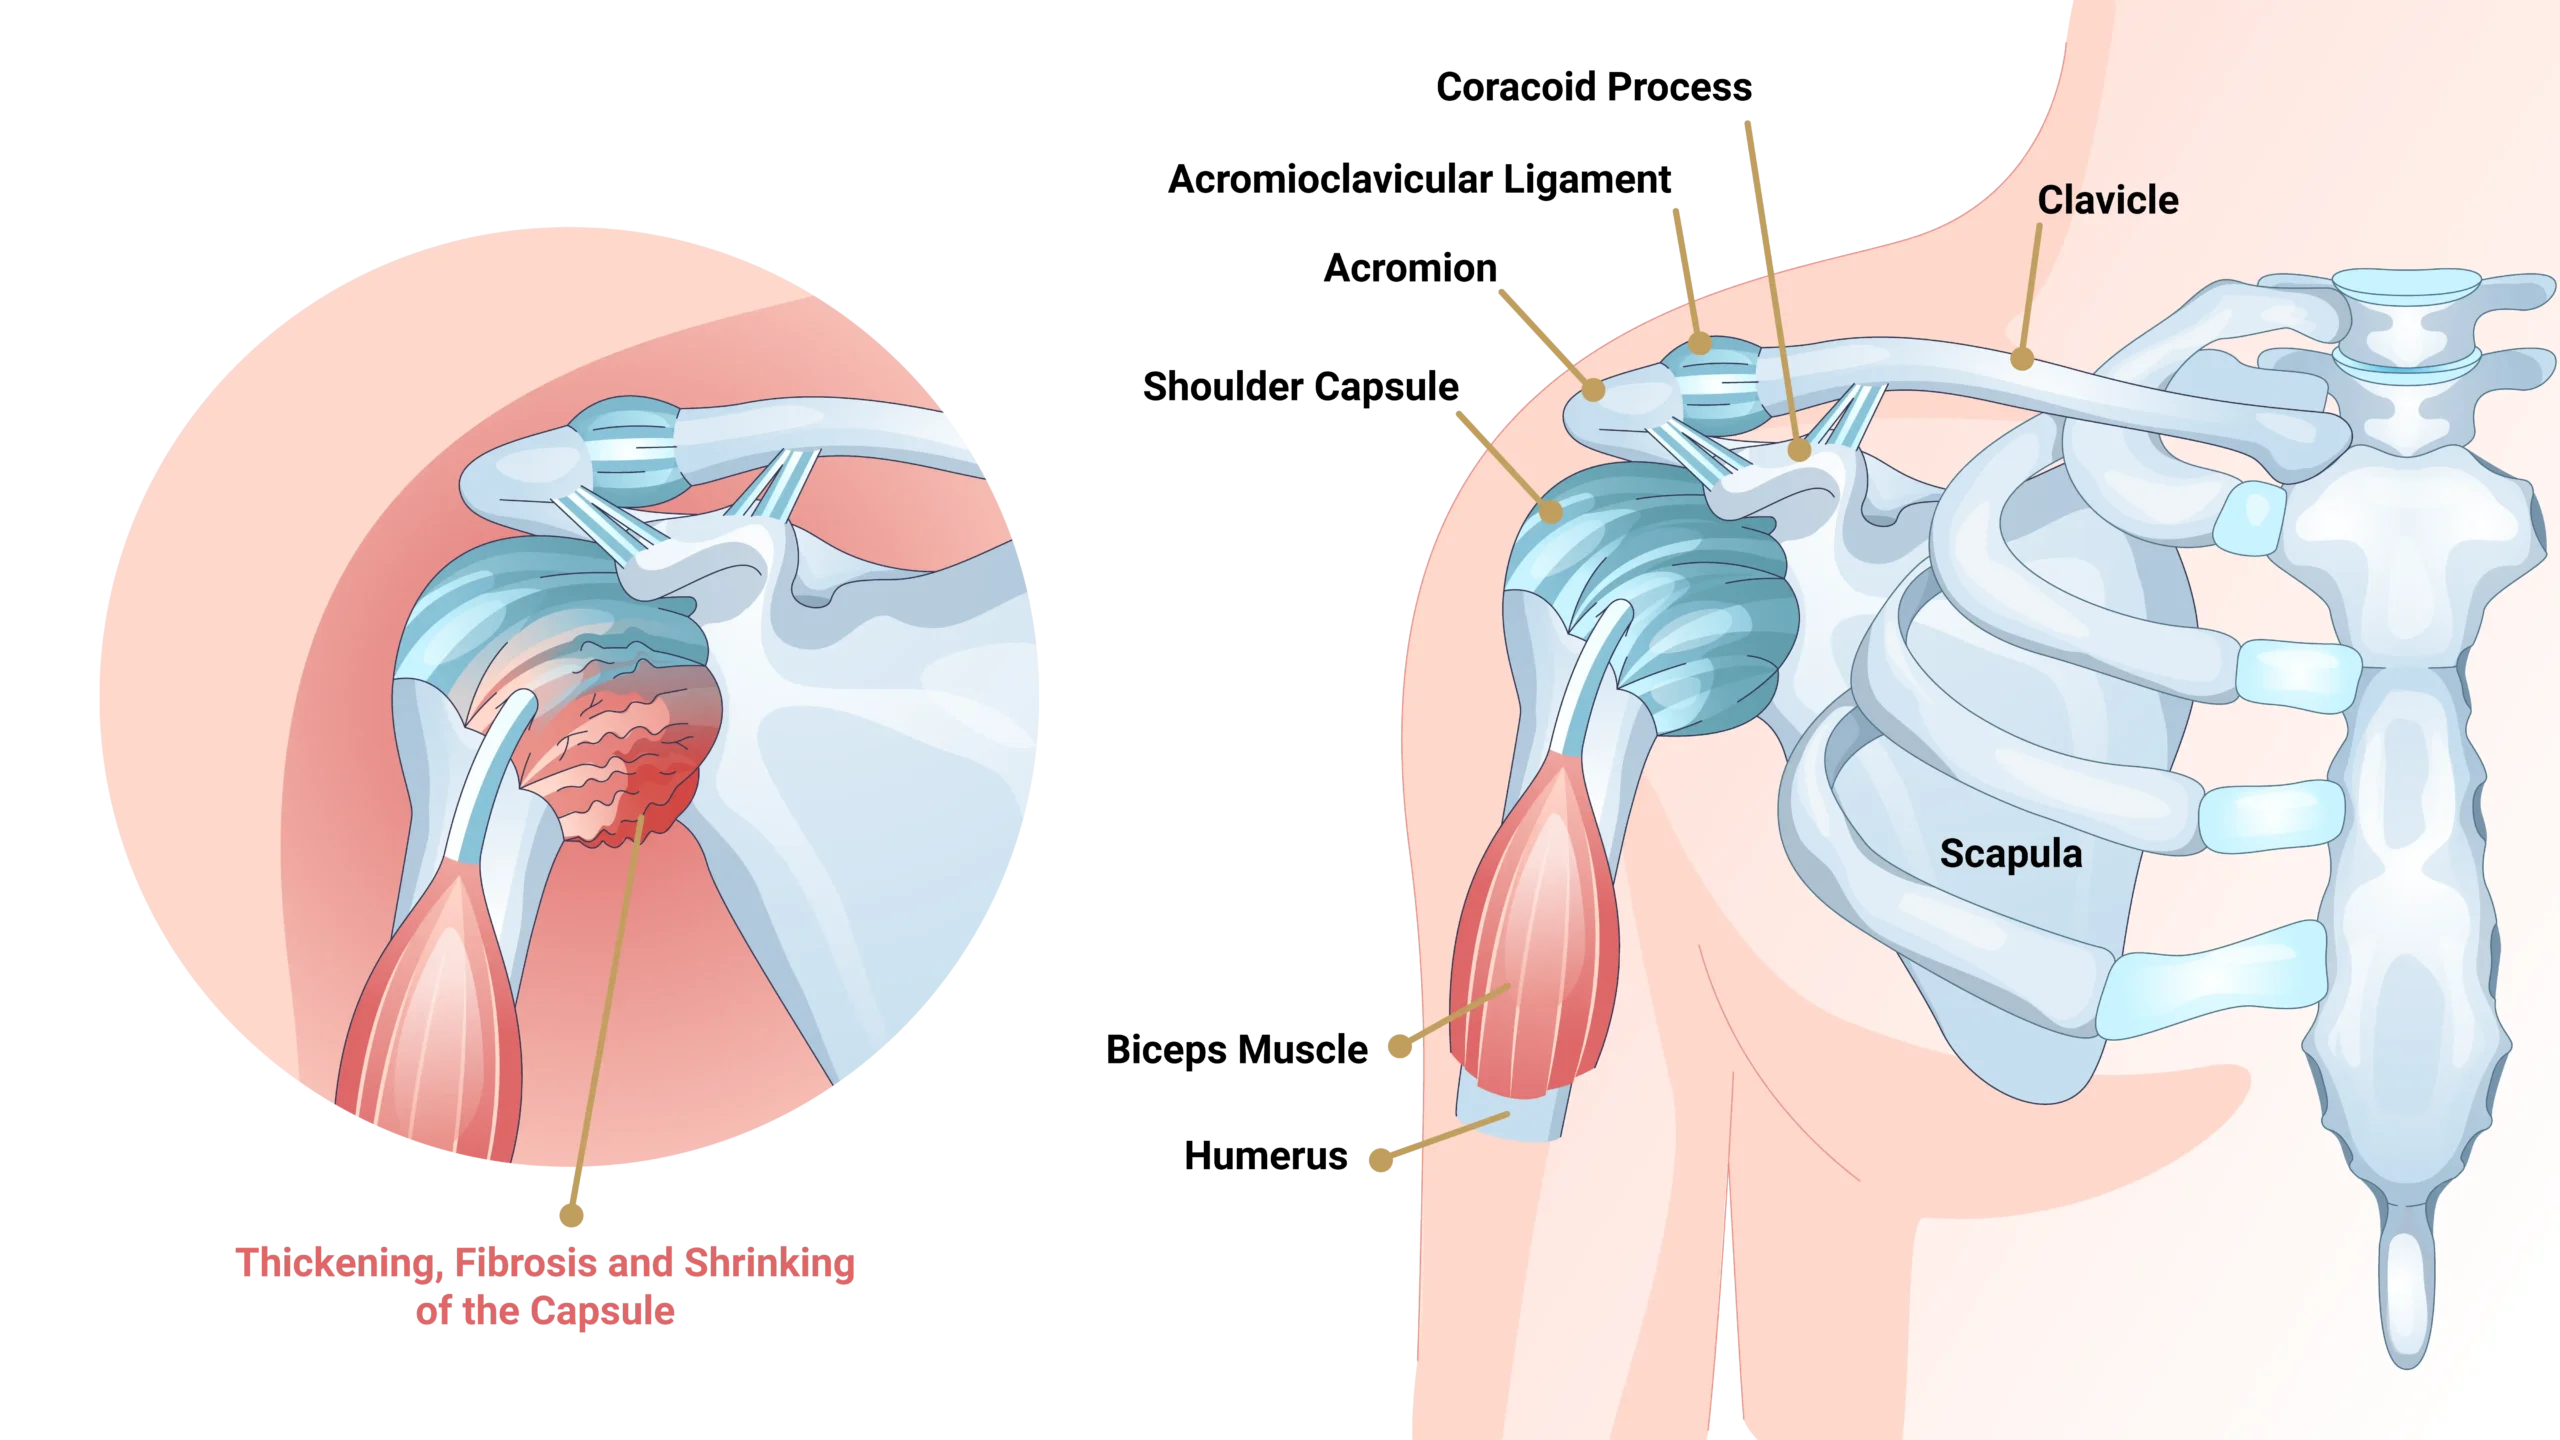

Frozen shoulder, clinically termed adhesive capsulitis, is a highly restrictive pathology targeting the connective tissue envelope of the joint.

The condition occurs when the shoulder joint capsule becomes profoundly inflamed, thickened, and contracted. This global capsular tightening severely restricts both active movement (you moving your arm) and passive movement (someone else moving your arm).

Unlike most subacromial or rotator cuff conditions where passive motion remains intact, frozen shoulder uniquely limits movement in all operational planes with a distinct, characteristic ‘hard stop’ mechanical block upon clinical testing.

What Causes Frozen Shoulder?

Frozen shoulder stems from advanced complex cellular transformations within the joint envelope, heavily stimulated by metabolic conditions and immobility markers.

Post-Injury Immobilization

Prolonged shoulder immobility acts as a major mechanical pathway trigger. Whether recovering from a rotator cuff tear repair, a stroke-induced hemiplegia profile, or undergoing extended sling dependency, joint disuse sparks an aggressive localized inflammatory cascade that quickly thickens the joint capsule.